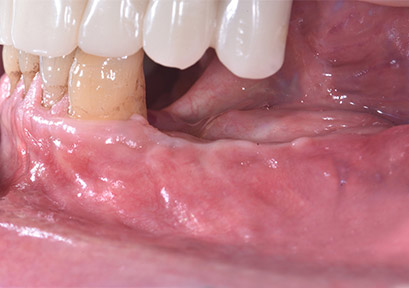

CASO LIVE SURGERY DEL 18 NOVEMBRE 2023

Eseguito dal Dottor Stefano Daina; estratto dal Corso "2 Live Surgery - GBR Verticale e Orizzontale dei Mascellari" del 17 e 18 Novembre 2023 svolto presso Daina Centro Odontostomatologico.

PRE INTERVENTO

POST INTERVENTO A 20 GIORNI